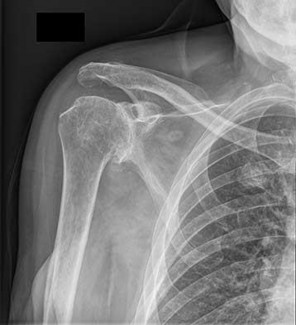

Question 10:

According to recent quantitative anatomical studies utilizing MRI and gadolinium, which of the following vessels provides the principal intraosseous blood supply to the humeral head, challenging historical teachings regarding proximal humerus vascularity?

Correct Answer: Posterior humeral circumflex artery

Explanation:

Historically, the anterior humeral circumflex artery (via its arcuate branch) was thought to be the primary blood supply to the humeral head. However, modern quantitative studies (e.g., Hettrich et al.) have demonstrated that the posterior humeral circumflex artery provides the vast majority (approximately 64%) of the intraosseous blood supply to the humeral head.